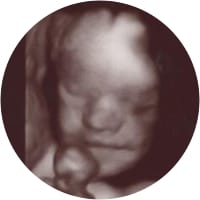

Lila Kaye Mitchell